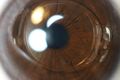

Anterior part of human eye, with anterior chamber at right. | |

الغرفة الأمامية ( AC ) هي المساحة المليئة بالخلط المائي داخل العين بين القزحية والسطح الداخلي للقرنية ، البطانة .[1] التحدمية والتهاب القزحية الأمامي والزرق هي ثلاثة أمراض رئيسية في هذا المجال. في التحدمية ، يملأ الدم الحجرة الأمامية نتيجة للنزيف ، وغالبًا ما يحدث بعد إصابة العين الحادة. التهاب العنبية الأمامي هو عملية التهابية تؤثر على القزحية والجسم الهدبي ، مع ظهور علامات التهابية في الحجرة الأمامية. في الزرق ، يمنع انسداد شبكة الصلبة التدفق الطبيعي للخلط المائي ، مما يؤدي إلى زيادة ضغط العين ، وتلف تدريجي في رأس العصب البصري ، وفي النهاية العمى .

يتراوح عمق الحجرة الأمامية للعين بين 1.5 و 4.0 ملم ، بمتوسط 3.0 مم. تميل إلى أن تصبح ضحلة مع تقدم العمر وفي العيون مع فرط طول النظر (بعد النظر) كلما انخفض العمق إلى أقل من 2.5 مم ، يزداد خطر الإصابة بزرق انسداد الزاوية.